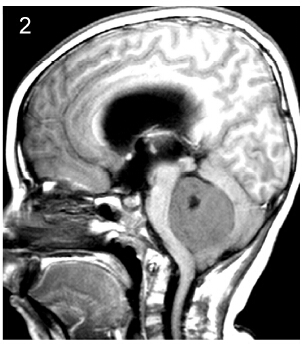

2 Patients and methods This study was approved by Ethics Committee of Tiantan Hospital, Capital Medical University. We retrospectively reviewed the medical records of all patients operated at our hospital between January 2004 and January 2007 who were diagnosed with medulloblastoma and were aged 16 years or older at diagnosis. Follow-up data were collected by telephone or follow-up visits at the clinic.Tumor location was defined as central or lateral on the basis of preoperative computed tomography and magnetic resonance neuroimaging findings and surgical reports (Figures 1-3). Because infiltration of the floor of the fourth ventricle was only observed in cases of centrally located tumors, we classified the tumors into three subtypes: those located at the midline without infiltration of the fourth ventricle floor, those located at the midline with infiltration of the fourth ventricle floor, and those located laterally.

| Figure 1 Subtype 1, Subtype 1: midline-located tumor without fourth ventricle floor infiltration. |